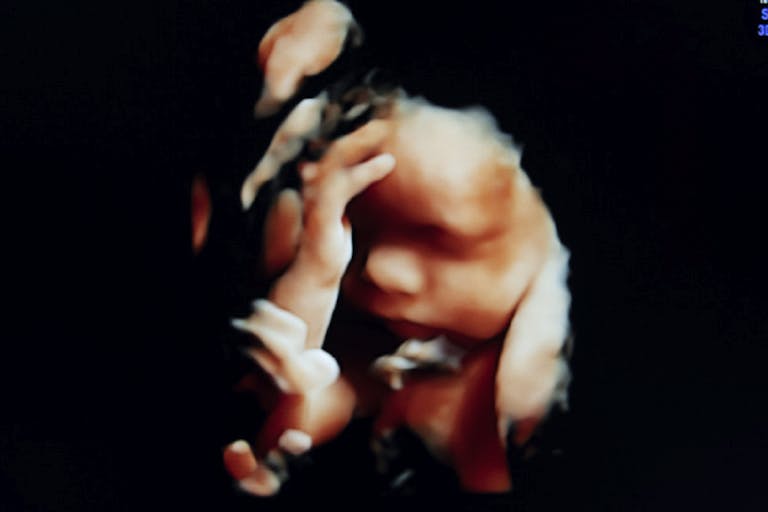

A woman in the UK has been sentenced to more than two years after she took abortion pills beyond the legal limit of 10 weeks, intentionally killing her baby beyond the legal limit of 24 weeks. She is believed to have been 32 weeks pregnant at the time she took the pills.

According to The Guardian, the woman, Carla Foster, was able to access the abortion pill regimen by mail by lying to the British Pregnancy Advisory Service (BPAS) — the UK’s largest abortion business — and saying she was less than 10 weeks pregnant. In reality, it is believed she was 28 weeks — which is about six to seven months — when she got the pills. However, after the child, Lily, was delivered, doctors determined she was at least 32 weeks. A coroner’s report revealed the baby did not breathe at birth.

However, if Foster were experiencing a medical emergency or the baby had received a diagnosis, abortion would have been completely legal (though intentional killing is unnecessary) in the hospital. Reid showed no concern for the baby who was “forcibly separated” from Foster, deliberately and knowingly killed well beyond the so-called age of viability. At 32 weeks, the baby was capable of surviving outside the womb but was intentionally killed by her mother.